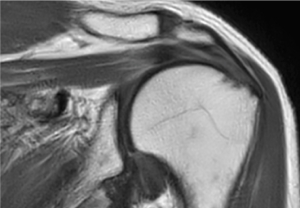

SmartSpeed は、空間分解能を最大 65% 向上させることができます¹。これにより、画像診断の精度を向上させるための情報を提供できます。

Philips SmartSpeed には優れたノイズ除去機能が搭載されており、スキャン時間を延長することなく、非常に高分解能のイメージングを実現できます。これは、血管系の小さな病変を描出する場合などに非常に重要です。"